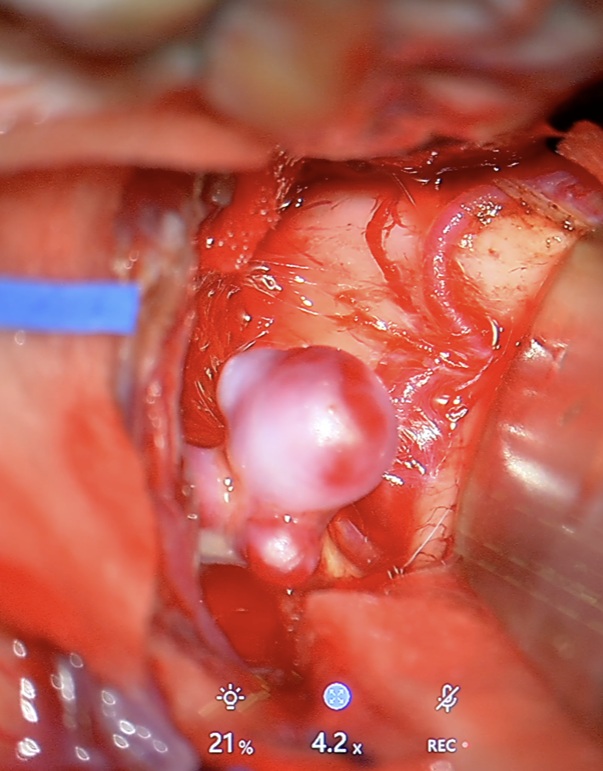

Klipsowanie chirurgiczne – metoda klasyczna

Jak przebiega zabieg?

Jest to operacja neurochirurgiczna, podczas której wykonuje się kraniotomię (czyli czasowe otwarcie fragmentu kości czaszki, aby uzyskać bezpieczny dostęp do mózgu). Pod mikroskopem operacyjnym neurochirurg zakłada tytanowy klips na szyję tętniaka, trwale odcinając dopływ krwi do jego wnętrza, przy jednoczesnym zachowaniu prawidłowego przepływu w naczyniu macierzystym (głównej tętnicy).